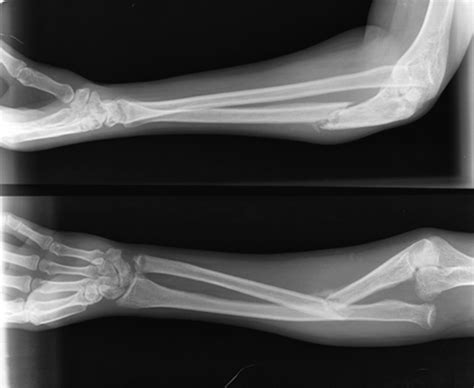

Alkūnės lūžis

Alkūnkaulio osteotomija

Kas yra alkūnkaulio osteotomija? Alkūnkaulio osteotomija - tai planinė operacija, kurios metu chirurgiškai perkerpamas ir perstatomas alkūnkaulis (ulna), siekiant atkurti taisyklingą rankos biomechaniką, sumažinti skausmą ar išspręsti sąnario spaudimą. Paprastai taikoma dėl alkūnės skausmų, nestabilumo ar po traumų.